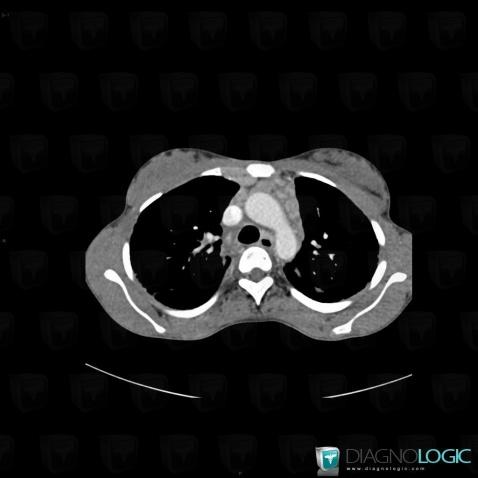

Sarcoïdose, Médiastin, Scanner

Voici les informations spécifiques à l'image clé ci dessus:

- Diagnostic Sarcoïdose, Localisation(s) Médiastin, comportant les gammes Masse médiastinale antérieure